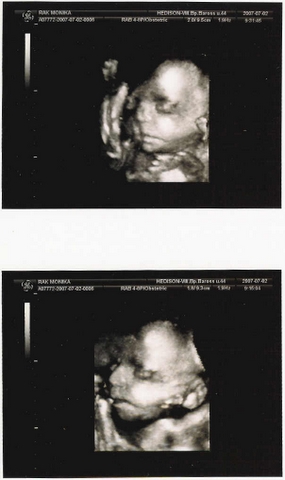

Zsu, ez a rajz valami frenetikus!!!!

gondolom, a csíkos téglalap a cél...?